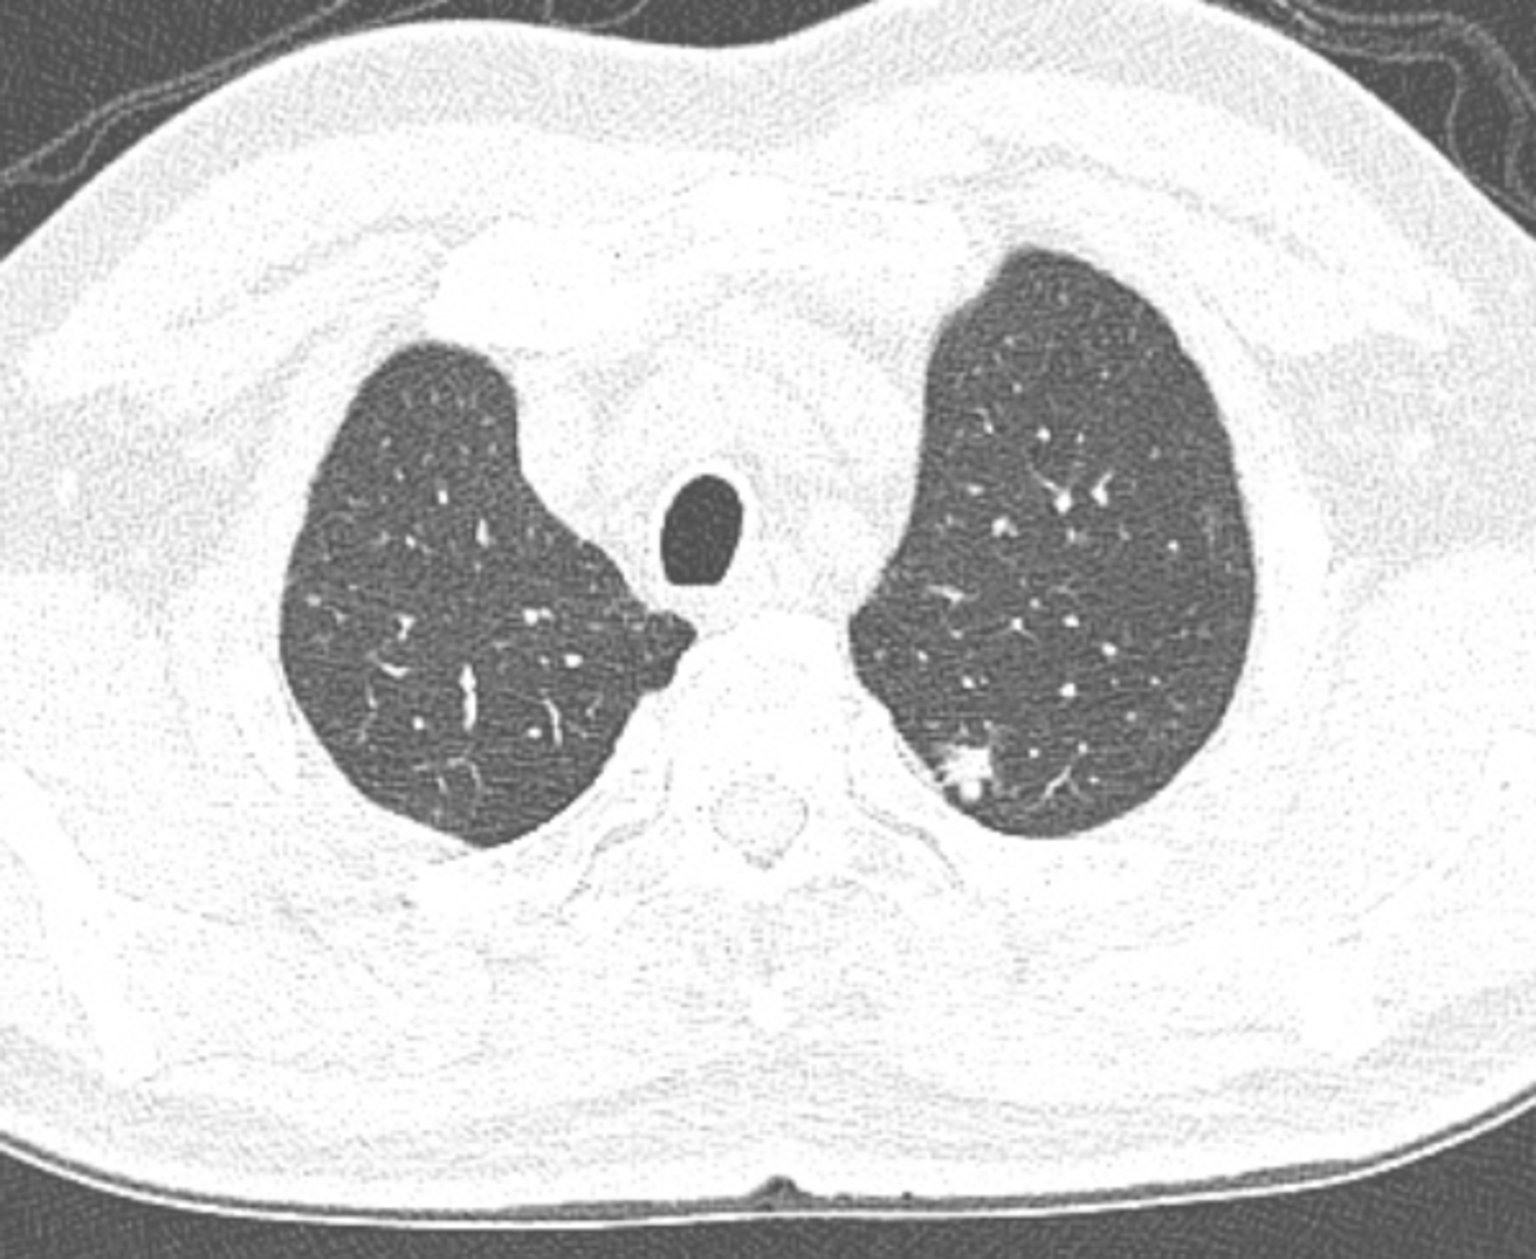

肺部淋巴结ct

ct经典图谱11:肺内淋巴结,你曾经遇到过,只是不知道

图片尺寸512x512